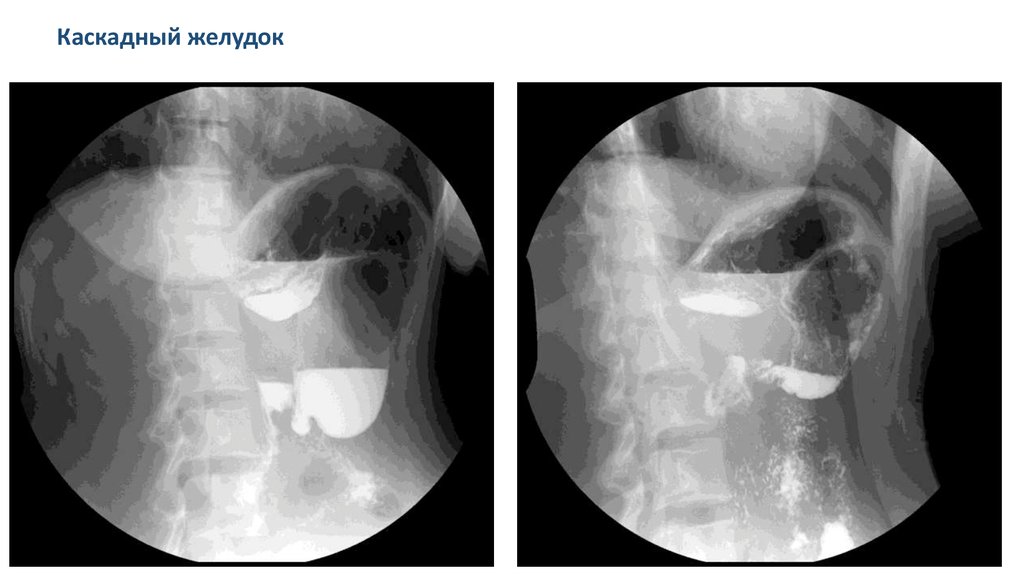

Каскадный желудок